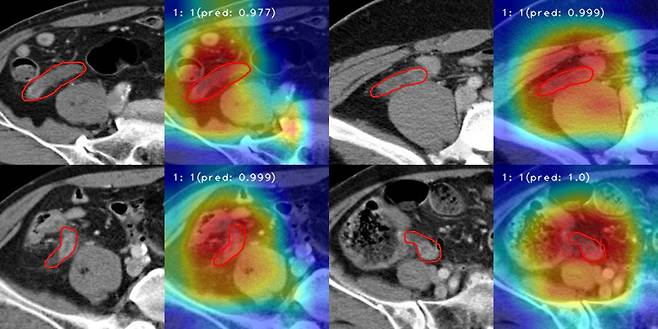

한림대성심병원 연구팀이 개발한 AI 모델은 CT 영상을 실시간으로 관찰해 충수염만 진단하는 게 가능하다. 대장염, 말단회장염, 상행결장게실염 등 충수염과 임상적으로 유사한 질환을 걸러내는 것이다.

이후 충수염 환자 1839명, 충수염이 아닌 것으로 진단받은 1782명의 데이터를 걸러내고 ‘3D 콘볼루션 신경망(CNN)’을 활용한 모델에 학습시켰다. 학습을 마친 AI 모델의 충수염 진단 정확도는 89.4%로 나타났다. AI 모델의 성능을 평가하는 데 사용하는 ‘곡선하면적(AUC)’ 점수는 0.890으로 집계됐다.

조범주 의료인공지능센터장은 “이번 AI는 기존 모델들과 달리 3차원 CT 영상을 입체적으로 인식했다는 점에서 의의가 있다”라고 설명했다.